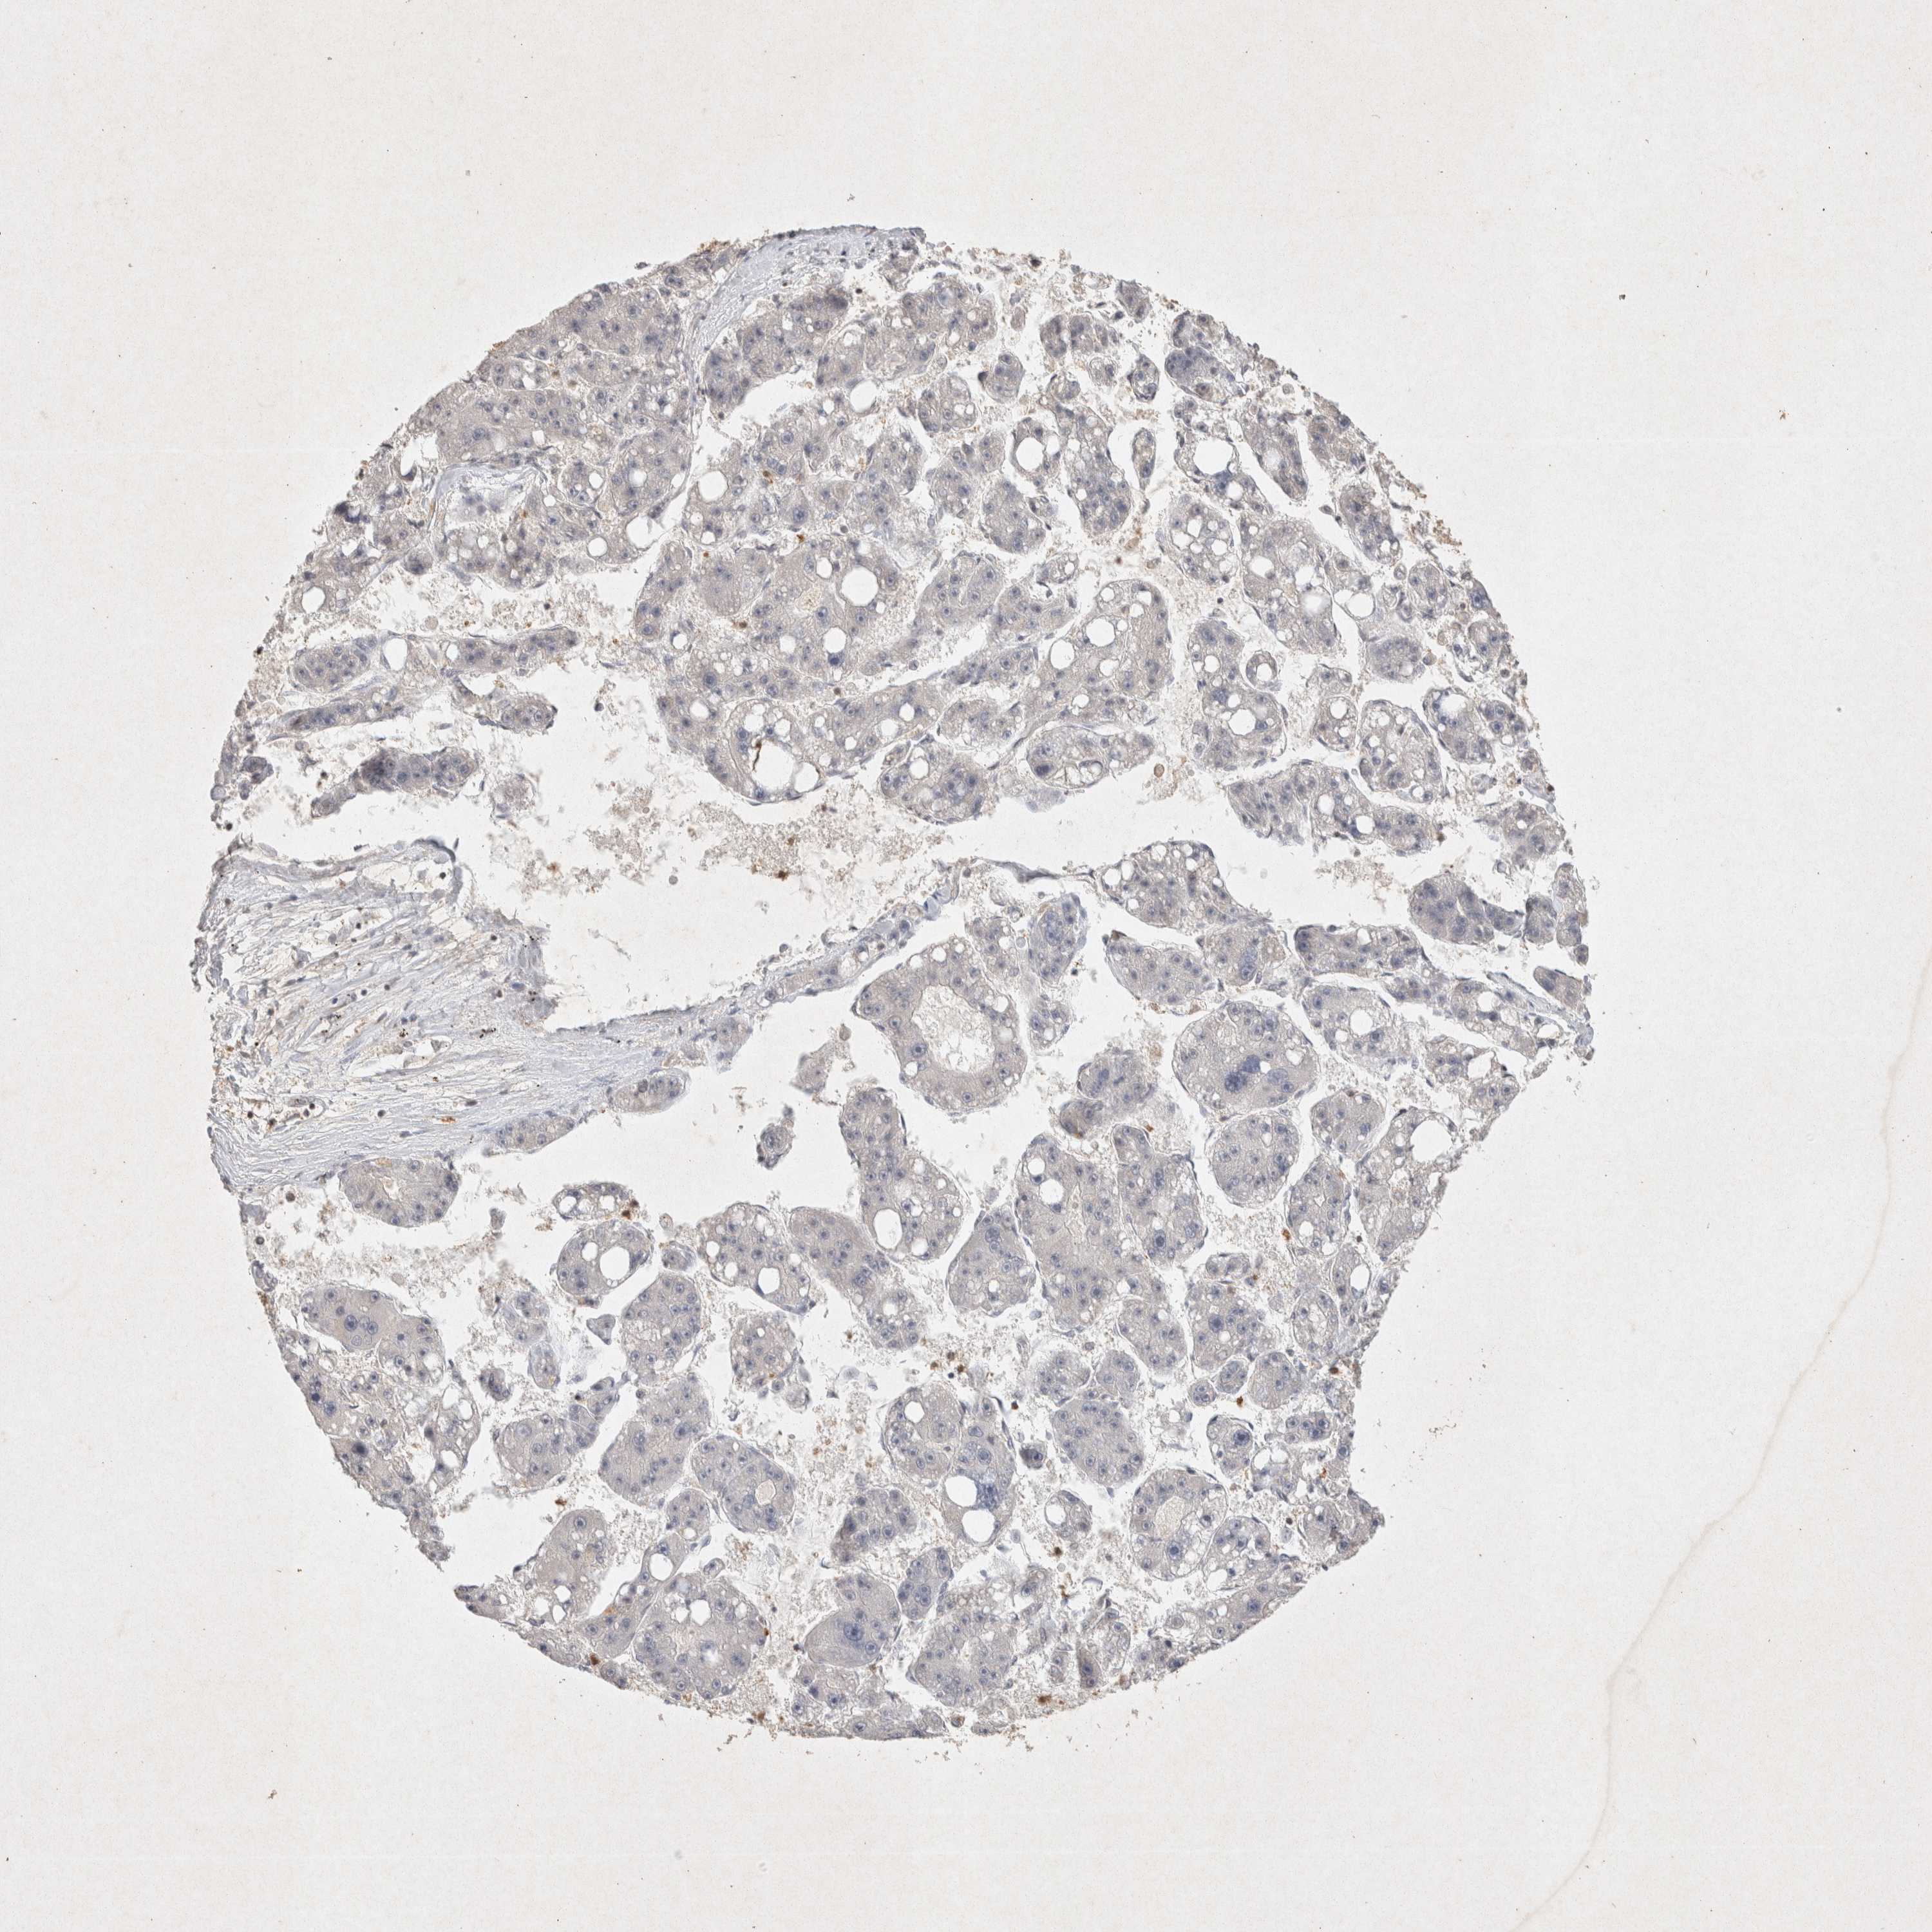

LIVER CANCER - Protein expressioni

A mouse-over function shows sample information and annotation data. Click on an image to view it in a full screen mode. Samples can be filtered based on level of antibody staining by selecting one or several of the following categories: high, medium, low and not detected. The assay and annotation is described here.

Note that samples used for immunohistochemistry by the Human Protein Atlas do not correspond to samples in the TCGA dataset.

Antibody stainingi

Antibody staining in the annotated cell types in the current human tissue is reported as not detected, low, medium, or high, based on conventional immunohistochemistry profiling in selected tissues. This score is based on the combination of the staining intensity and fraction of stained cells.

Each image is clickable and will lead to virtual microscopy that enables deeper exploration of all samples and also displays staining intensity scores, fraction scores and subcellular localization as well as patient and tissue information for each sample.

Antibody HPA047820

Antibody CAB022946

Staining

High

Medium

Low

Not detected

Intensity

Strong

Moderate

Weak

Negative

Quantity

>75%

75%-25%

<25%

None

Location

Nuclear

Cytoplasmic/membranous

Cytoplasmic/membranous,nuclear

Cholangiocarcinoma

Carcinoma, Hepatocellular, NOS